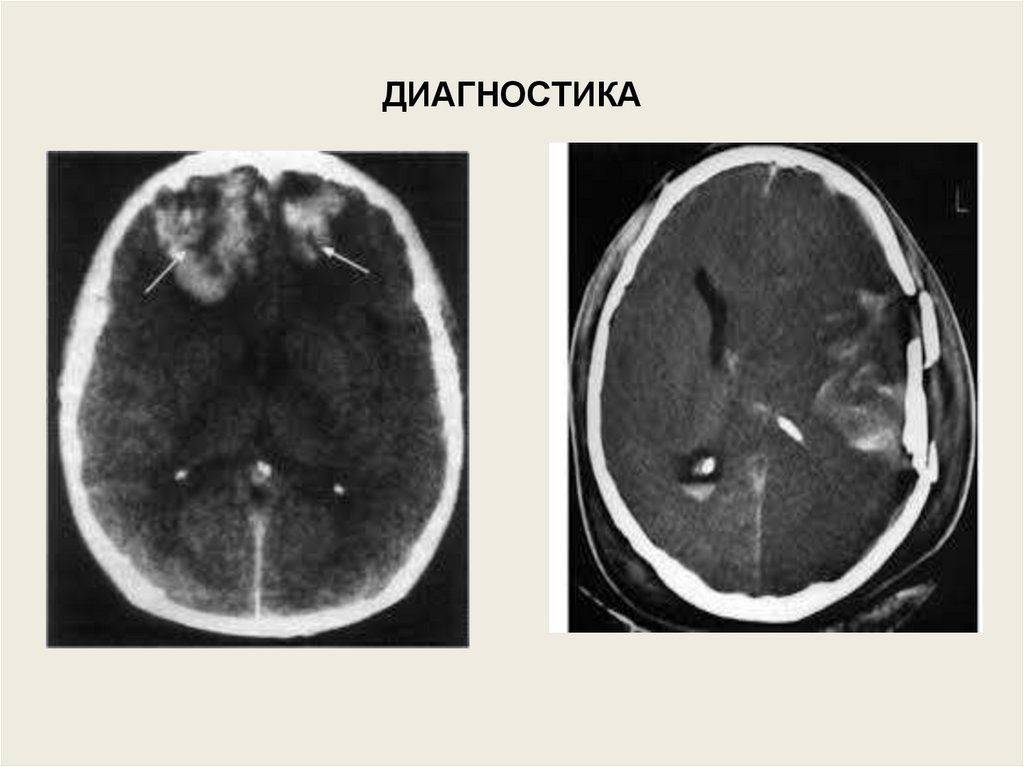

ДИАГНОСТИКА

• Для диагностики

используются

рентгенография черепа,

офтальмоскопия,

люмбальная пункция,

компьютерная

томография.